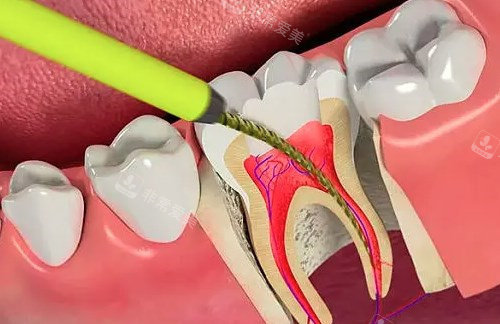

根管治疗ct照片

根管治疗动画图